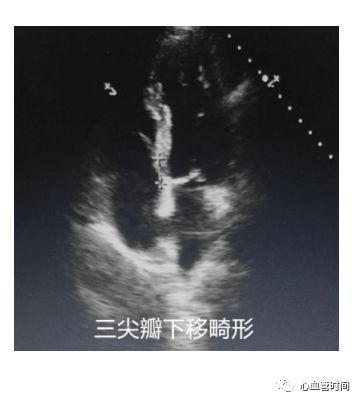

三尖瓣注意有无三尖瓣下移畸形。

三尖瓣注意有无三尖瓣下移畸形。